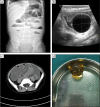

Management of foreign bodies ingestion in children